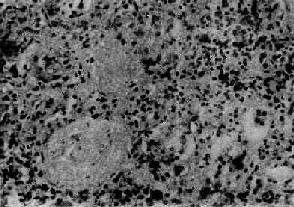

【病理变化】

光学显微镜下,肾小球无明显变化或仅有轻度节段性系膜增生。电镜下见弥漫性肾小球脏层上皮细胞足突消失(图12-20),细胞内高尔基器和内质网增多,并可见脂滴。细胞表面常有多数微绒毛形成。足突消失不仅见于脂性肾病,也常见于其他原因引起的大量蛋白尿和肾病综合征。经过治疗或蛋白尿等症状缓解后,脏层上皮细胞的变化可恢复正常。

图12-20 轻微病变性肾小球肾炎

电镜下见肾小球毛细血管上皮细胞部分足突消失